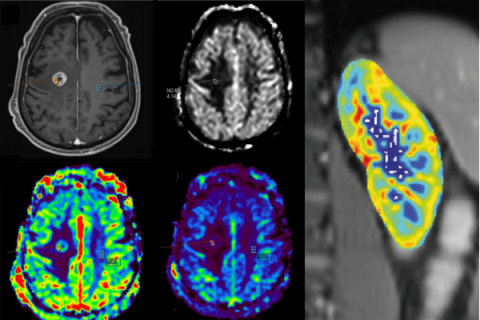

Perfusion and permeability

- Arterial Spin Labelling (ASL)

- Dynamic contrast-enhanced MRI (DCE) [not usable for healthy volunteers]

- Dynamic susceptibility contrast MRI (DSC) [not usable for healthy volunteers]

- Intravoxel incoherent motion (IVIM)